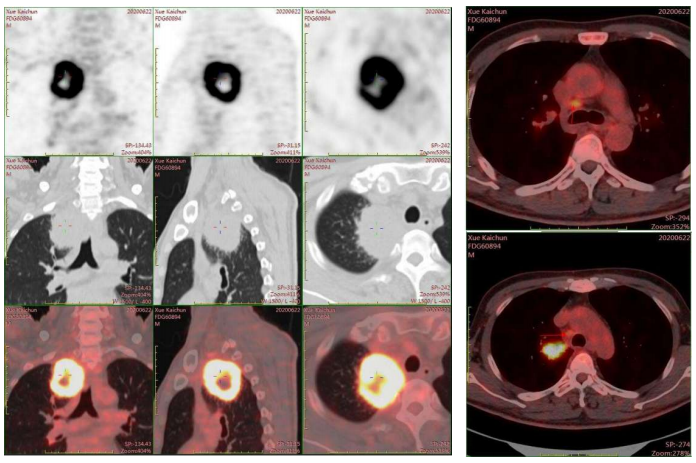

分期检查:PET/CT显示右肺上叶近纵隔处高代谢肿块(约5.6×5.3cm),侵犯纵隔胸膜,伴纵隔4R及右肺门淋巴结转移。脑MRI未见转移。

图1 PET-CT影像.png

图1 PET-CT影像